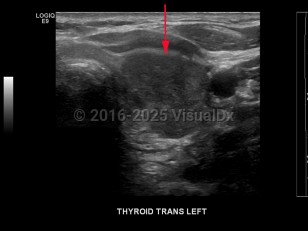

Signs and symptoms include a neck lump or swelling, neck pain, hoarseness, dysphagia, dyspnea, and/or persistent cough. Erythroderma may rarely be a cutaneous manifestation of malignancy.

Thyroid cancer is classified based on histologic features:

- Follicular thyroid cancer – The most common type of thyroid cancer in iodine-deficient regions of the world. It is often difficult to diagnose with fine-needle aspiration due to a lack of distinguishing features. Prognosis is poor if diagnosis is made at an advanced stage of disease.